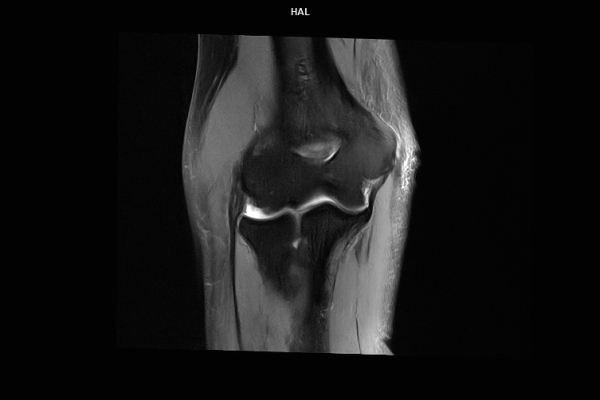

Detailbild MRT

• Muskuloskelettale Bildgebung

Die MRT (Magnetresonanztomographie) arbeitet mit Magnetfeldern und Radiowellen und eignet sich besonders für Untersuchungen der Weichteile wie Gehirn, Muskeln oder Gelenke. Die CT (Computertomographie) nutzt Röntgenstrahlen und liefert schnelle, hochauflösende Bilder, insbesondere für Knochen, Lunge oder innere Organe. Die Wahl der jeweiligen Untersuchung richtet sich an das individuelle Krankheitsbild und wird bei der Überweisung festgelegt.